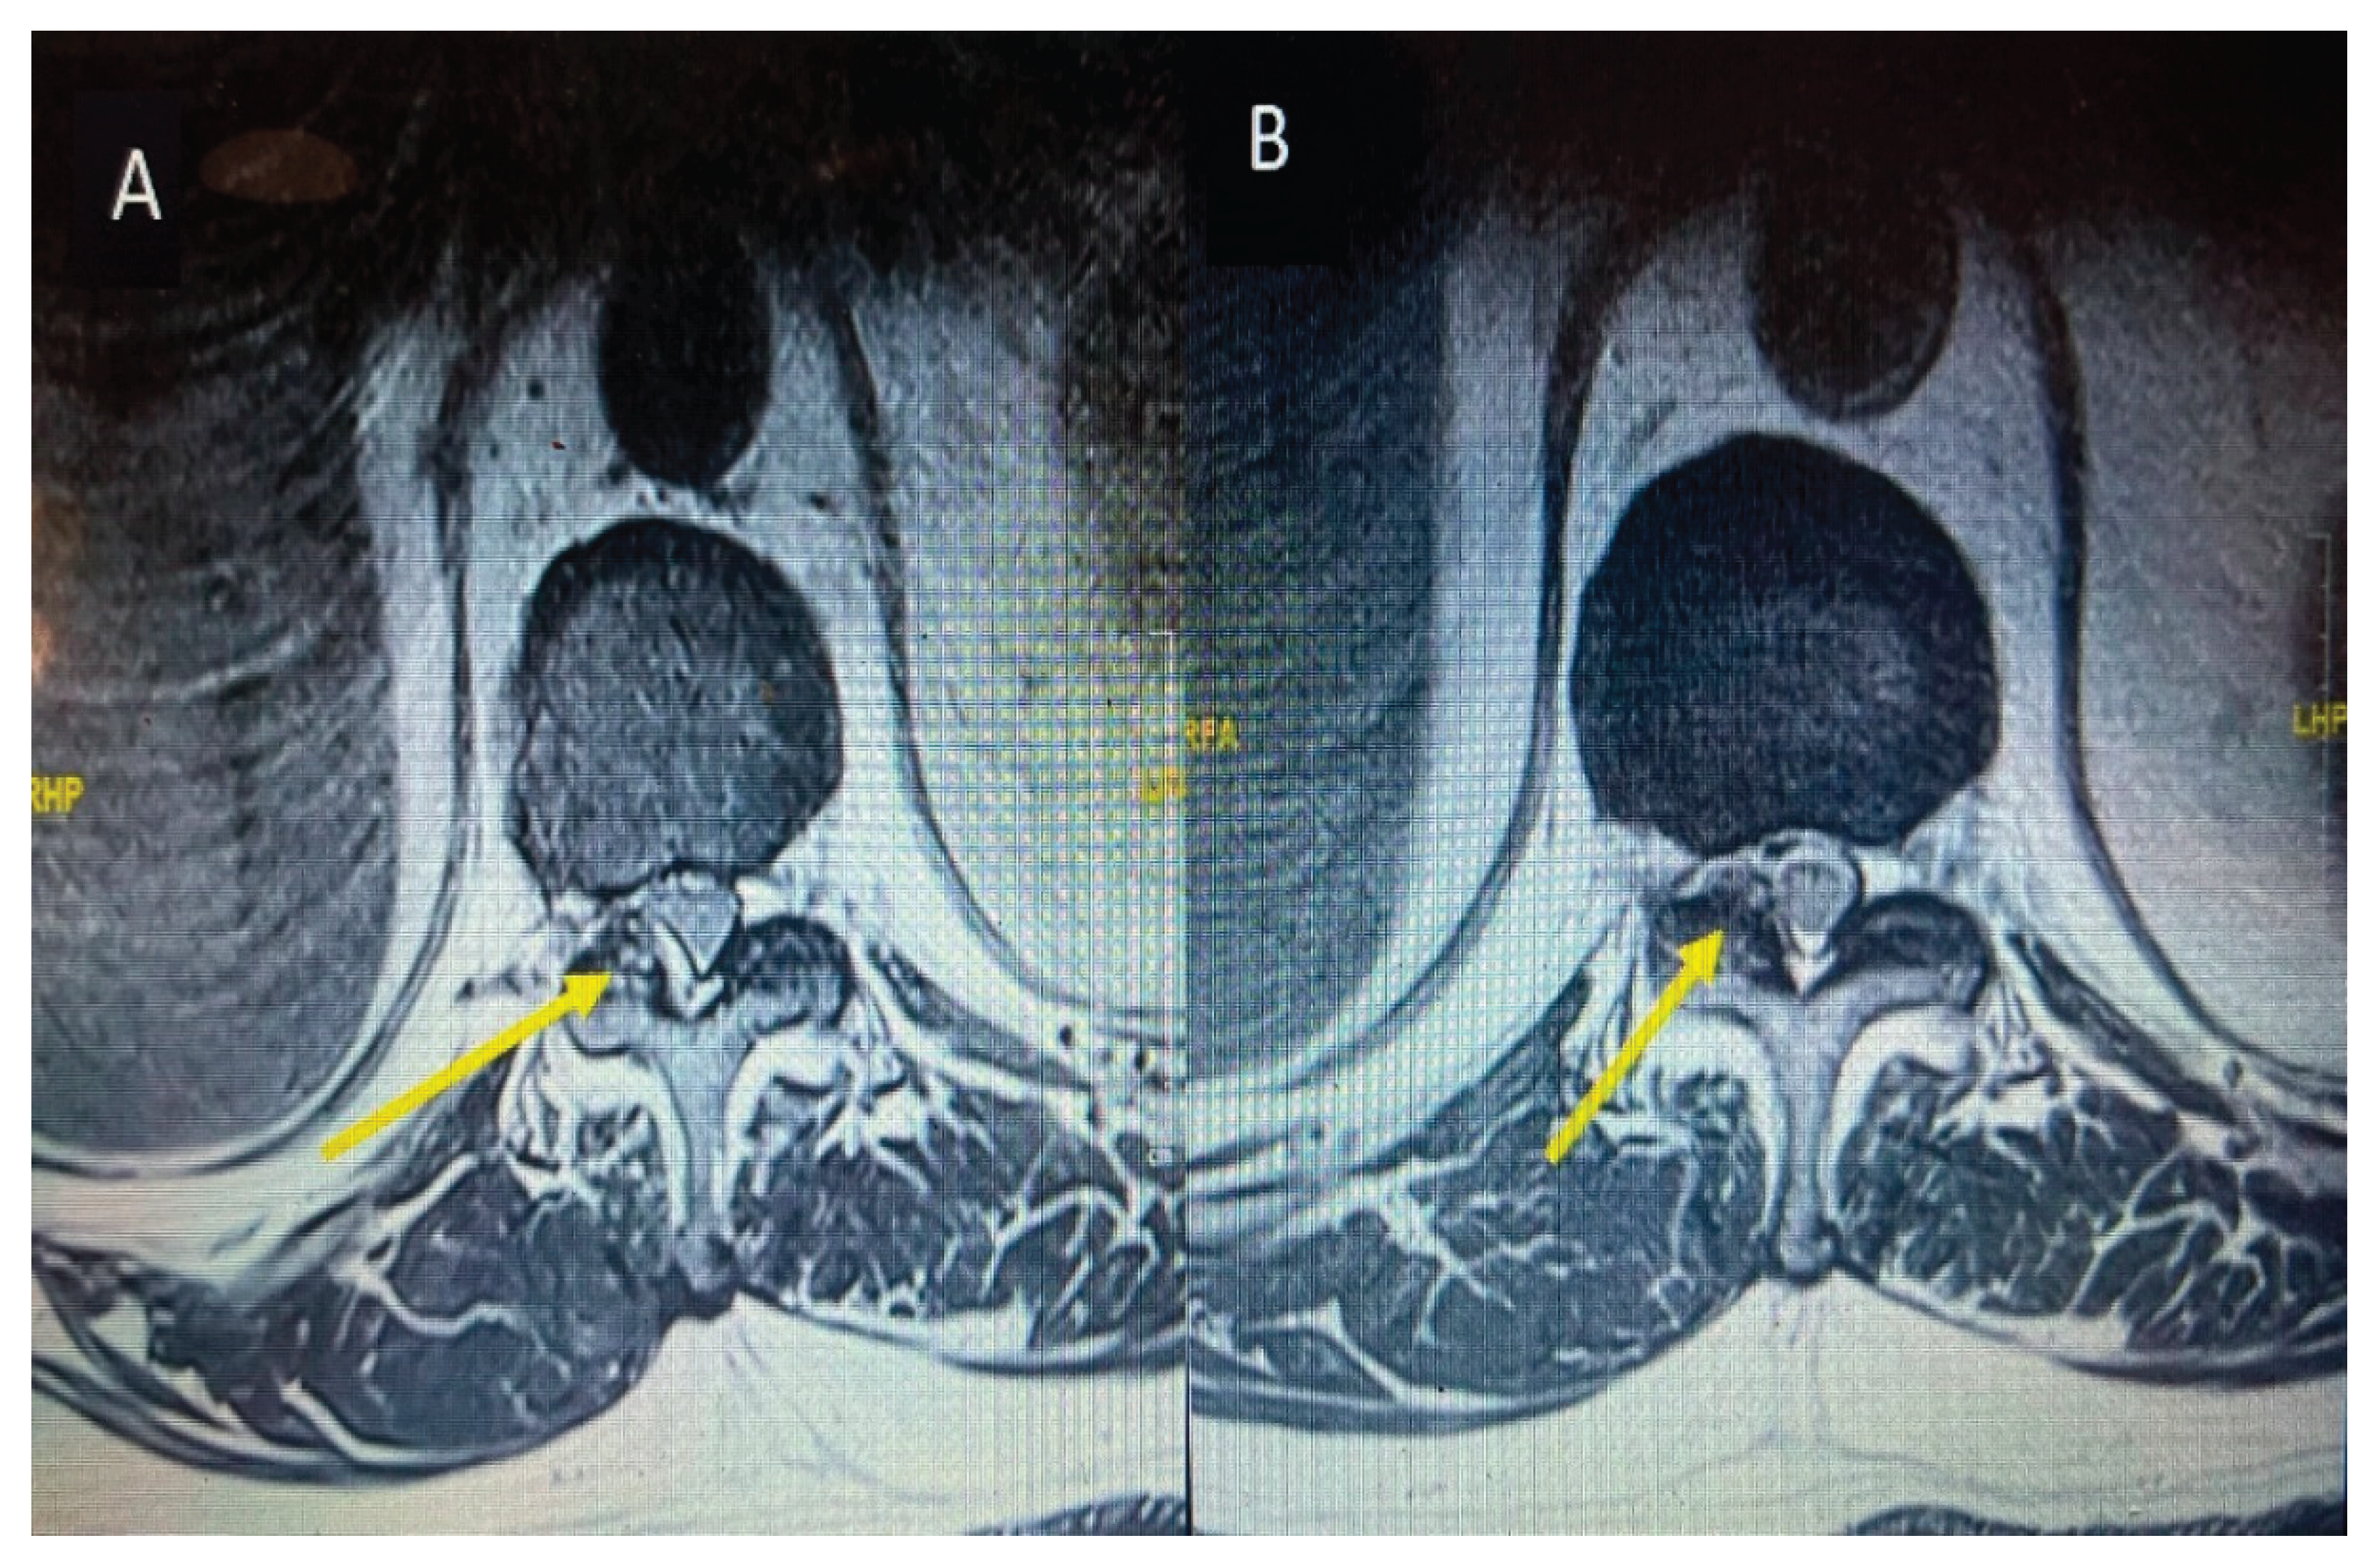

Inflammatory markers showed raised CRP level of 292. Meanwhile Hip and Knee team advised X Rays both knees reported as bilateral osteoarthritis with bilateral moderate to large suprapatellar effusion. Later on, they did bilateral knee joints aspiration and sent aspirate for laboratory evaluation which showed raised nucleated cells (35415), neutrophils (92%) and negatively birefringent crystals Based on knee joint aspiration result the patient was referred to Rheumatology for further assessment and serum Uric acid was sent as per their suggestion showed raised level of 532. Patient was counselled for image guided biopsy of the reported levels on MRI spine in order to exclude infective spondylodiscitis and septic arthritis but due to patient reluctance it was not done. While keeping in mind the patient clinical, radiological and lab tests picture dual energy CT whole spine was done reported as Urate deposits at the T10/11 and lower lumbar discs especially at L5/S1. Green pixelation in the rest of the thoracolumbar spine appears to represent artifact rather than further urate deposits. In particular, there does not appear to be urate deposits at the region of right the right T11/12 facet joint as shown in the Figure 7 (A) and (B). In order to start a definitive treatment, image guided biopsy was discussed with the patient but not done due to patient reluctance. Meanwhile multidisciplinary meeting was held between Infectious disease and Rheumatology teams while keeping in mind the differential diagnosis and a conclusion was made to treat the patient for Gout. Rheumatology team started the patient on 3 weeks tapering dose of prednisolone followed by 5 mg OD dose for few months for Gout prophylaxis. He was also started on Allopurinol an anti-Gout medication with a dose of 50 mg OD. Later on, Patient was transferred under the care of rehabilitation team. Patient CRP and serum Uric acid were trended over the time and showed progressive declined in their levels along with clinical improvement. Follow up MRI lumbar and thoracic spine revealed improvement in the form of slight signals improvement at L5/S1 shown in Figure 5 (B) and disappearance of right T10/11 facet cyst shown in the Figure 8 (B). After completing rehabilitation, the patient was discharged to the home with the follow up schedule with different concerned specialties.

Figure 8. MRI thoracic spine T2 weighted at the level of T10/11 axial section before starting anti gout. Medications (A) and axial section of follow up MRI after starting anti gout medications (B) showing a cyst on the right side as indicated by yellow arrow and total disappearance as shown by yellow arrow after starting anti gout medications.

Preprints 170211 g008

Spinal Gout cases are treated either conservatively or surgically based on presence or absence of neurological deficit. Pharmacological treatment is reserved for less severe cases without having signs and symptoms of radiculopathy and myelopathy. Medications such as NSAIDS, Colchicine and corticosteroids are used mainly used for symptoms relief in acute attacks without effecting deposition of tophi in tissues and boney erosions. If the patient has a history of hypertension, heart disease, chronic kidney disease, gastric or duodenal ulcers, NSAIDS allergy and receiving anticoagulant therapy then colchicine should be used in spite of NSAIDS. Anti gout medications which are divided into first- and second-lines medications are used to prevent further gout attacks with a goal to keep uric acid level less than 6 mg/dl. First line anti Gout medications mainly reduce uric acid production which include Xanthine oxidase inhibitors include allopurinol, oxypurinol and febuxostat and second line medications are Uricosuric agents which increase uric acid excretion having sulfinpyrazone and probenecid in the list. Surgical treatment is indicated when there is spinal cord or nerve roots compression with neurological deficit. The main goal of the surgery is to decompress the spinal cord and nerves with removal of tophi which looks like chalky white material [17]. We did decompression of the cervical spine in our first case with removal of chalky white material during the surgery because radiological images were showing compression of cervical spinal cord with progressive neurological deficit and the 2nd case was managed conservatively because the patient gave a good response to anti gout medications with improvement in clinical symptoms, declining uric acid level and complete resolution of thoracic spine facet cyst on follow up MRI spine.